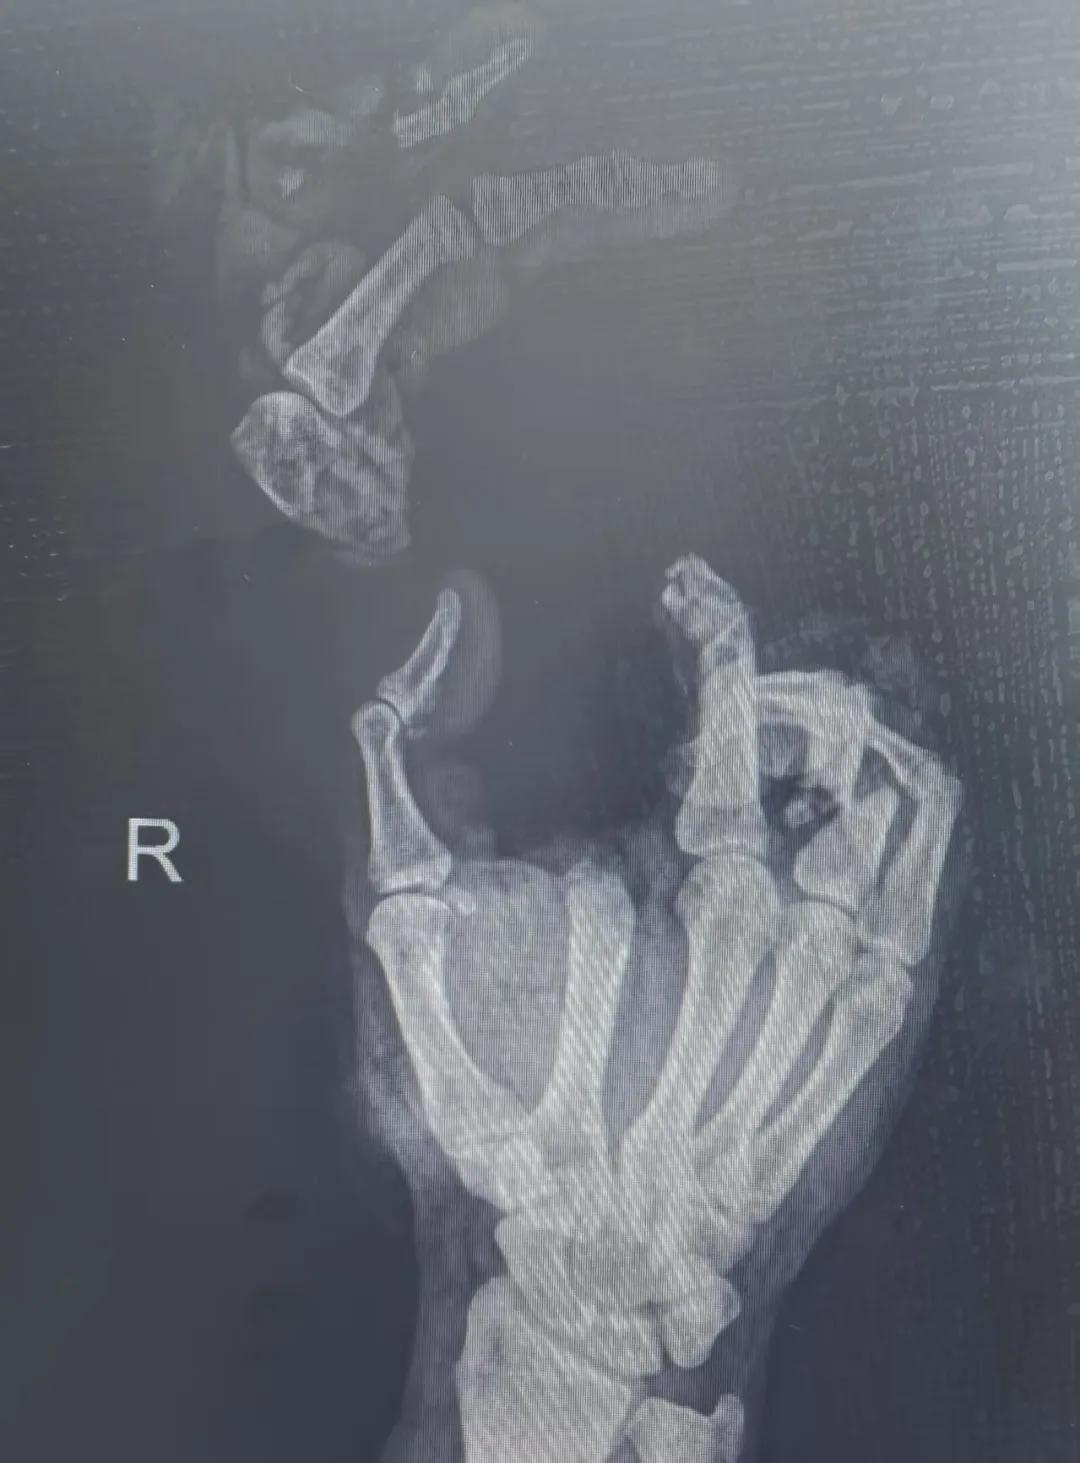

5月20日,市二院顯微外科燒傷整形科收治了3例因麥收被農機“咬傷”、農具劃傷的患者。其中,56歲的劉某在收麥子時被打谷機皮帶絞傷右手,致手掌、食指、中指、環指嚴重毀損傷,骨、關節外露,因當地醫院無法治療,被家人緊急送往市二院顯微手足燒傷整形外科救治。“當時整個右手血肉模糊,看上去都是爛的,我以為這個手是肯定保不住了。”患者家屬回憶當時的場景仍然膽戰心驚。

患者入院后,經X線檢查及創面檢查,醫生診斷為右手食指、中指及環指旋轉撕脫性離斷。接診的顯微手足燒傷整形外科醫護人員立即完善了各項術前準備,并安排急診手術。因創面污染嚴重以及離斷肢體損傷程度較重,手術歷時近10小時。在沈衛軍主任的帶領下,科室團隊成功為其進行了創面擴創、斷肢再植術,術后患指血運良好,在進一步觀察治療中。